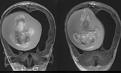

Fetus of twin is surgically removed from the SKULL of one-year-old sister in China - after she went to doctor with an enlarged head and cognitive problems.